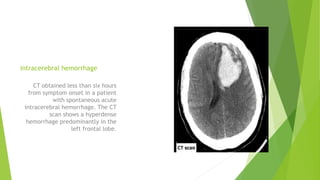

intracerebral hemorrhage

CT obtained less than six hours

from symptom onset in a patient

with spontaneous acute

intracerebral hemorrhage. The CT

scan shows a hyperdense

hemorrhage predominantly in the

left frontal lobe.

intracerebral hemorrhage CT obtainedless than six hours from symptom onset in a patient with spontaneous acute intracerebral hemorrhage. The CT scan shows a hyperdense hemorrhage predominantly in the left frontal lobe.